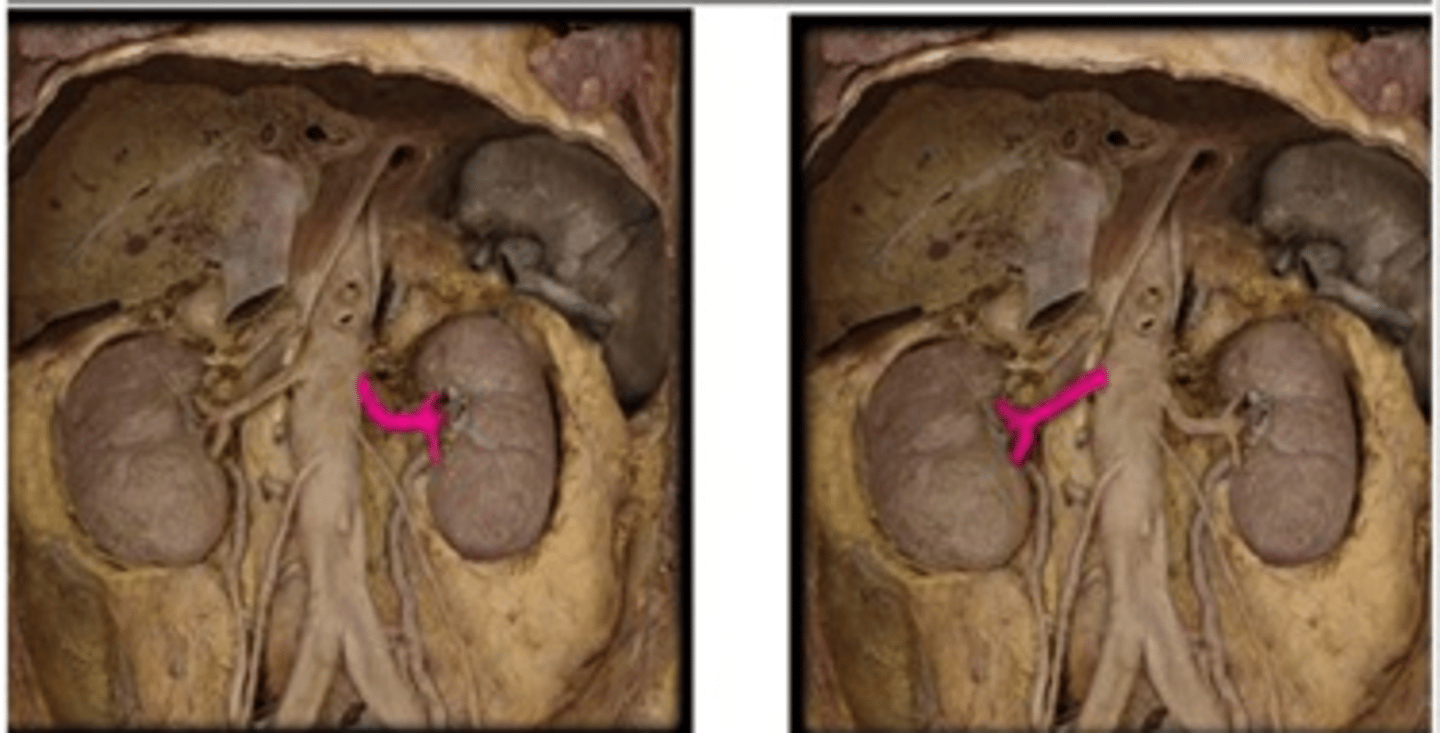

right renal arteries

the right is on top. we have to flip the kidney.

left renal arteries

below the kidney for left.